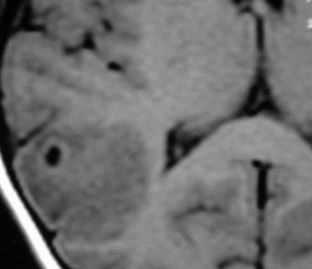

При нейроцистицеркозе на МРТ головного мозга наблюдается гидроцефалия и “разбросанные” мелкие очаги, часто с кальцификацией.

МРТ головного мозга. Т1-взвешенная аксиальная МРТ. Нейроцистицеркоз.